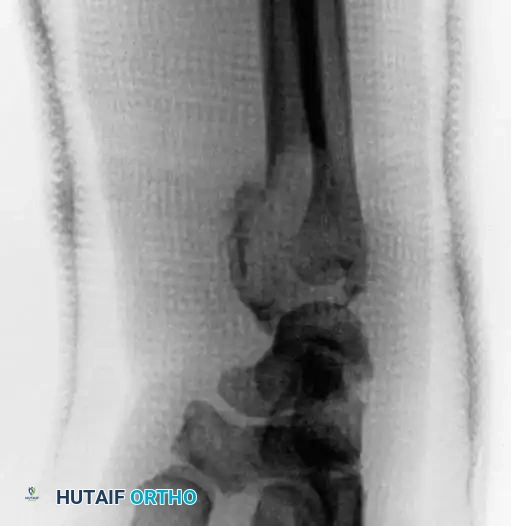

Plain Radiography

On plain radiographs, chondroblastoma typically appears as a well-circumscribed, eccentrically or centrally located lytic lesion confined to the epiphysis or apophysis. A defining feature is the presence of a surrounding rim of reactive sclerotic bone. Intralesional calcification—often described as a stippled or "fluffy" chondroid matrix—is visible on plain films in 30% to 50% of cases.

In skeletally immature patients, a well-circumscribed epiphyseal lesion that crosses an open physis (growth plate) into the metaphysis is virtually diagnostic of chondroblastoma.

In cases involving the distal radius (a common site for aggressive epiphyseal tumors like GCT), en bloc resection of the distal radius is performed. The tumor is excised with wide margins, sacrificing the radiocarpal joint.

To reconstruct the defect and restore forearm length, a structural autograft is harvested. The contralateral proximal fibula is an excellent anatomical match for the distal radius.

The fibular autograft is contoured and impacted into the medullary canal of the remaining radial diaphysis. A rigid wrist fusion plate is then applied dorsally, spanning from the radial shaft, across the fibular graft, and securing to the carpal bones (typically the capitate and third metacarpal) to achieve a stable radiocarpal arthrodesis.